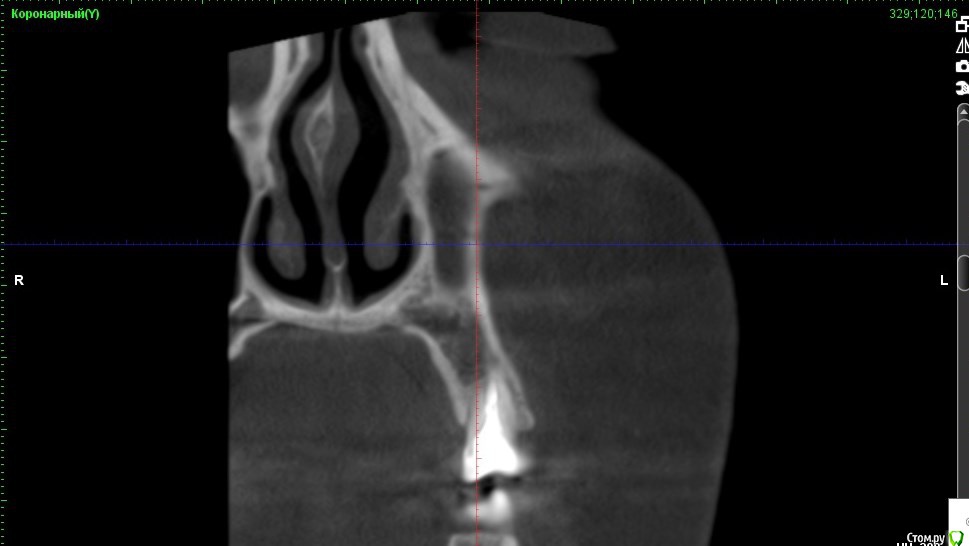

Verasss Опубликовано 8 октября, 2016 Автор Поделиться Опубликовано 8 октября, 2016 КТ от 08.09. Извините, что в таком виде, надо менять ОЗУ. Ссылка на комментарий

Verasss Опубликовано 28 октября, 2016 Автор Поделиться Опубликовано 28 октября, 2016 Добрый вечер! Ещё раз попытаюсь прикрепить скриншоты КТ от сентября. Если качество совсем не устраивает, подскажите, пожалуйста, какие сделать снимки?К сожалению, программа не позволяет вывести снимки на полный экран и заскриншотить в более хорошем качестве. Ссылка на комментарий

Verasss Опубликовано 28 октября, 2016 Автор Поделиться Опубликовано 28 октября, 2016 еще снимки Ссылка на комментарий

Verasss Опубликовано 28 октября, 2016 Автор Поделиться Опубликовано 28 октября, 2016 и еще Ссылка на комментарий

DmitrySH Опубликовано 8 октября, 2016 Поделиться Опубликовано 8 октября, 2016 В таком виде КТ малоинформативно. Но гайморита нет. Ссылка на комментарий

Verasss Опубликовано 23 ноября, 2016 Автор Поделиться Опубликовано 23 ноября, 2016 Сделала ещё 1 кт, спустя почти 2,5 месяца после первого. Посмотрите, пожалуйста, есть ли изменения? Напомню, что пункцию гайморовой мне сделали. Ссылка на комментарий